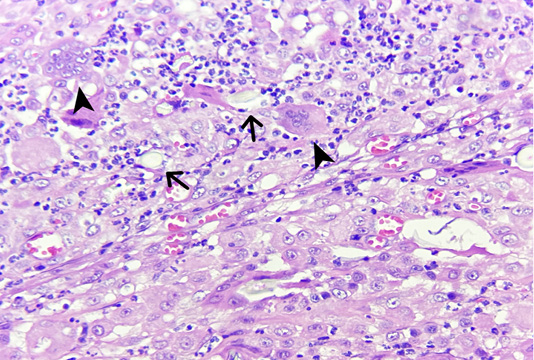

Figure 2

Trichogranuloma in a cat. Cutaneous nodule. There are fragments of free hair shaft (arrows) surrounded by giant foreign body cells (arrow heads) and leukocytic infiltration. (400 X, H&E).